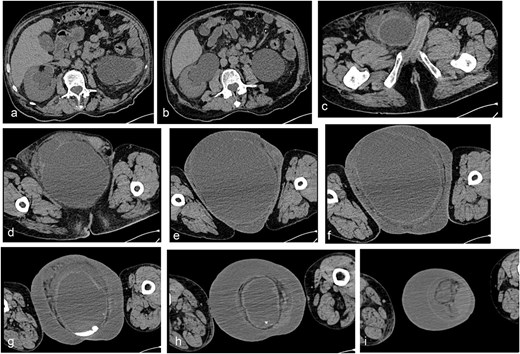

A non-contrast pelvic computed tomography (CT) scan was performed to evaluate a palpable right inguinal mass. The CT revealed an aponeurotic defect in the right inguinal region with protrusion of the urinary bladder into the right inguinal canal, completely lodging in the scrotal sac. This finding was associated with increased scrotal volume, striations of the periscrotal fat, and thickening of the scrotal wall by 25 mm. Significant dilation of the renal collecting system was also observed, measuring 40 mm on the right side and 62 mm on the left, with an increase in the diameter of the ureters. The bladder presented dimensions of 240 × 173 × 194 mm with a volume of 4212 mL, completely full and entirely located within the right scrotal sac. The findings indicate the presence of a right inguinoscrotal vesical hernia with bilateral dilation of the pelvicalyceal system, possibly exacerbated by maximum bladder filling (Fig. 3a–d, h, and i).

Simple abdominopelvic CT scan slices showing significant dilation of the renal collecting system, measuring 40 mm on the right side and 62 mm on the left, with an increase in the diameter of the ureters (a–c), an aponeurotic defect in the right inguinal region with protrusion of the urinary bladder into the inguinal canal (d–f), and the bladder completely full and entirely located within the right scrotal sac (g–i).